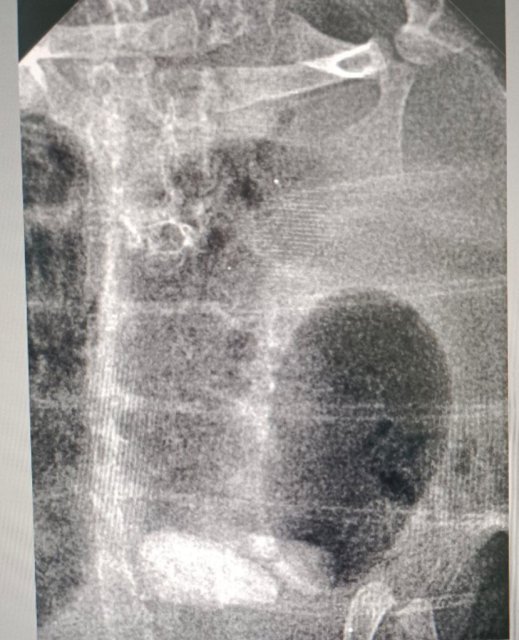

А раздуло черепашку от слишком частого кормления и последующего бездействия с ее стороны. Она очень часто ела айсберг, а от айсберга, оказывается, черепах пучит. Это вообще единственный салат от которого пучит, и нашей он очень нравится =) Врач рентген сделал, вся черная область - это газы в кишечнике, которые не выходили из-за пассивного поведения. Сказали кормить объемом в 1/3 панциря, пока отек не спадет полностью, а айсберг на время исключить.

19.02 мы таки попали на прием к Бойцовой и результат был неутешительный - подозрение на рахит. Изначально врач сказала, что панцирь стал немного мягче, а когда решили посмотреть динамику лечения раздутого кишечника на рентгене, увидели, что "значительно снижена плотность костных структур". Отсюда и мягкий панцирь, и странные зависания при ходьбе. (лечение желудка при этом идет хорошо)